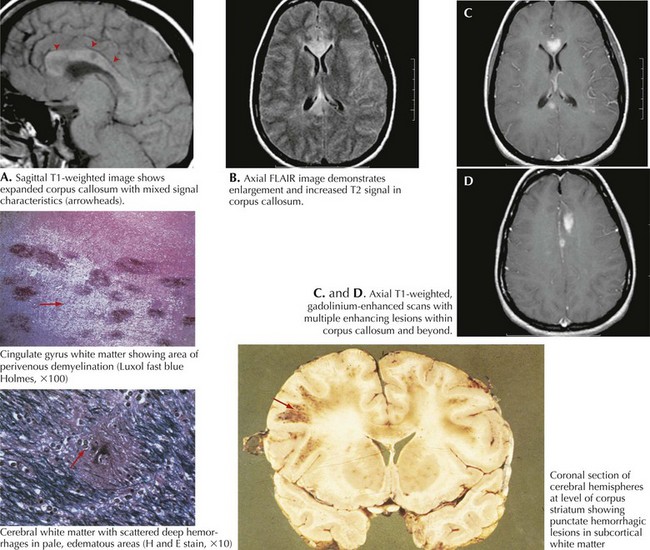

Multiple sclerosis is a chronic relapsing disease of the central nervous system, which is characterized by the formation of multiple scattered foci of demyelination in the brain and spinal cord.

A distinctive feature of this disease is the presence of foci of sclerosis scattered throughout the central nervous system without a specific localization – the replacement of normal nervous tissue with connective tissue.

Diagnosis

Diagnosis of multiple sclerosis is based mainly on the identification of 2 clinical features:

- Undulating course – alternation of exacerbations and remissions in the remitting form, fluctuations in the rate of progression in the progredient form.

- Multifocal lesion of the white matter of the brain.

Paraclinical data support the diagnosis.